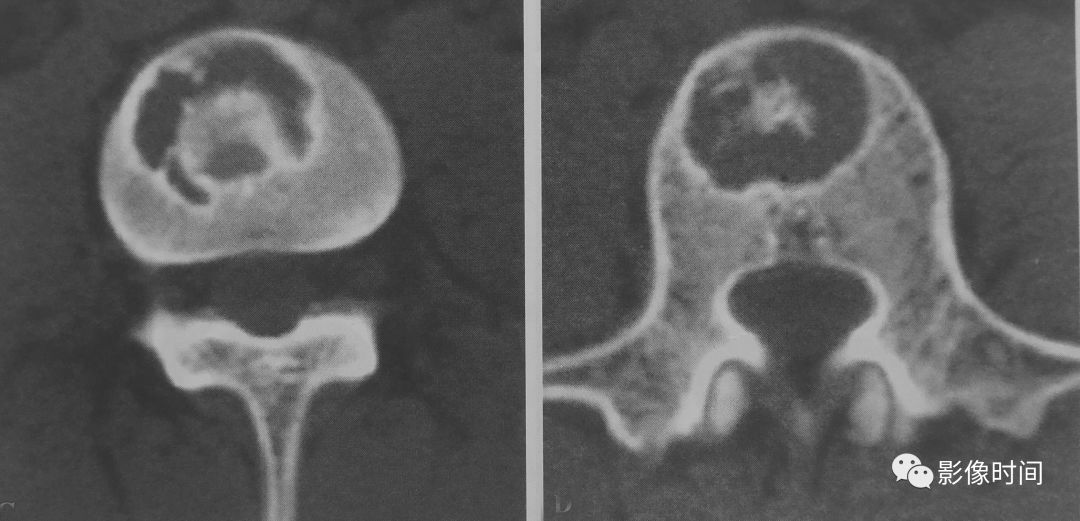

骨肿瘤中富含黏液基质有软骨黏液样纤维瘤(图 28)、黏液纤维肉瘤、黏液软骨肉瘤和脊索瘤(图 29)等。

图 28  粘液样基质:软骨粘液样纤维瘤

图 29  粘液样基质:脊索瘤